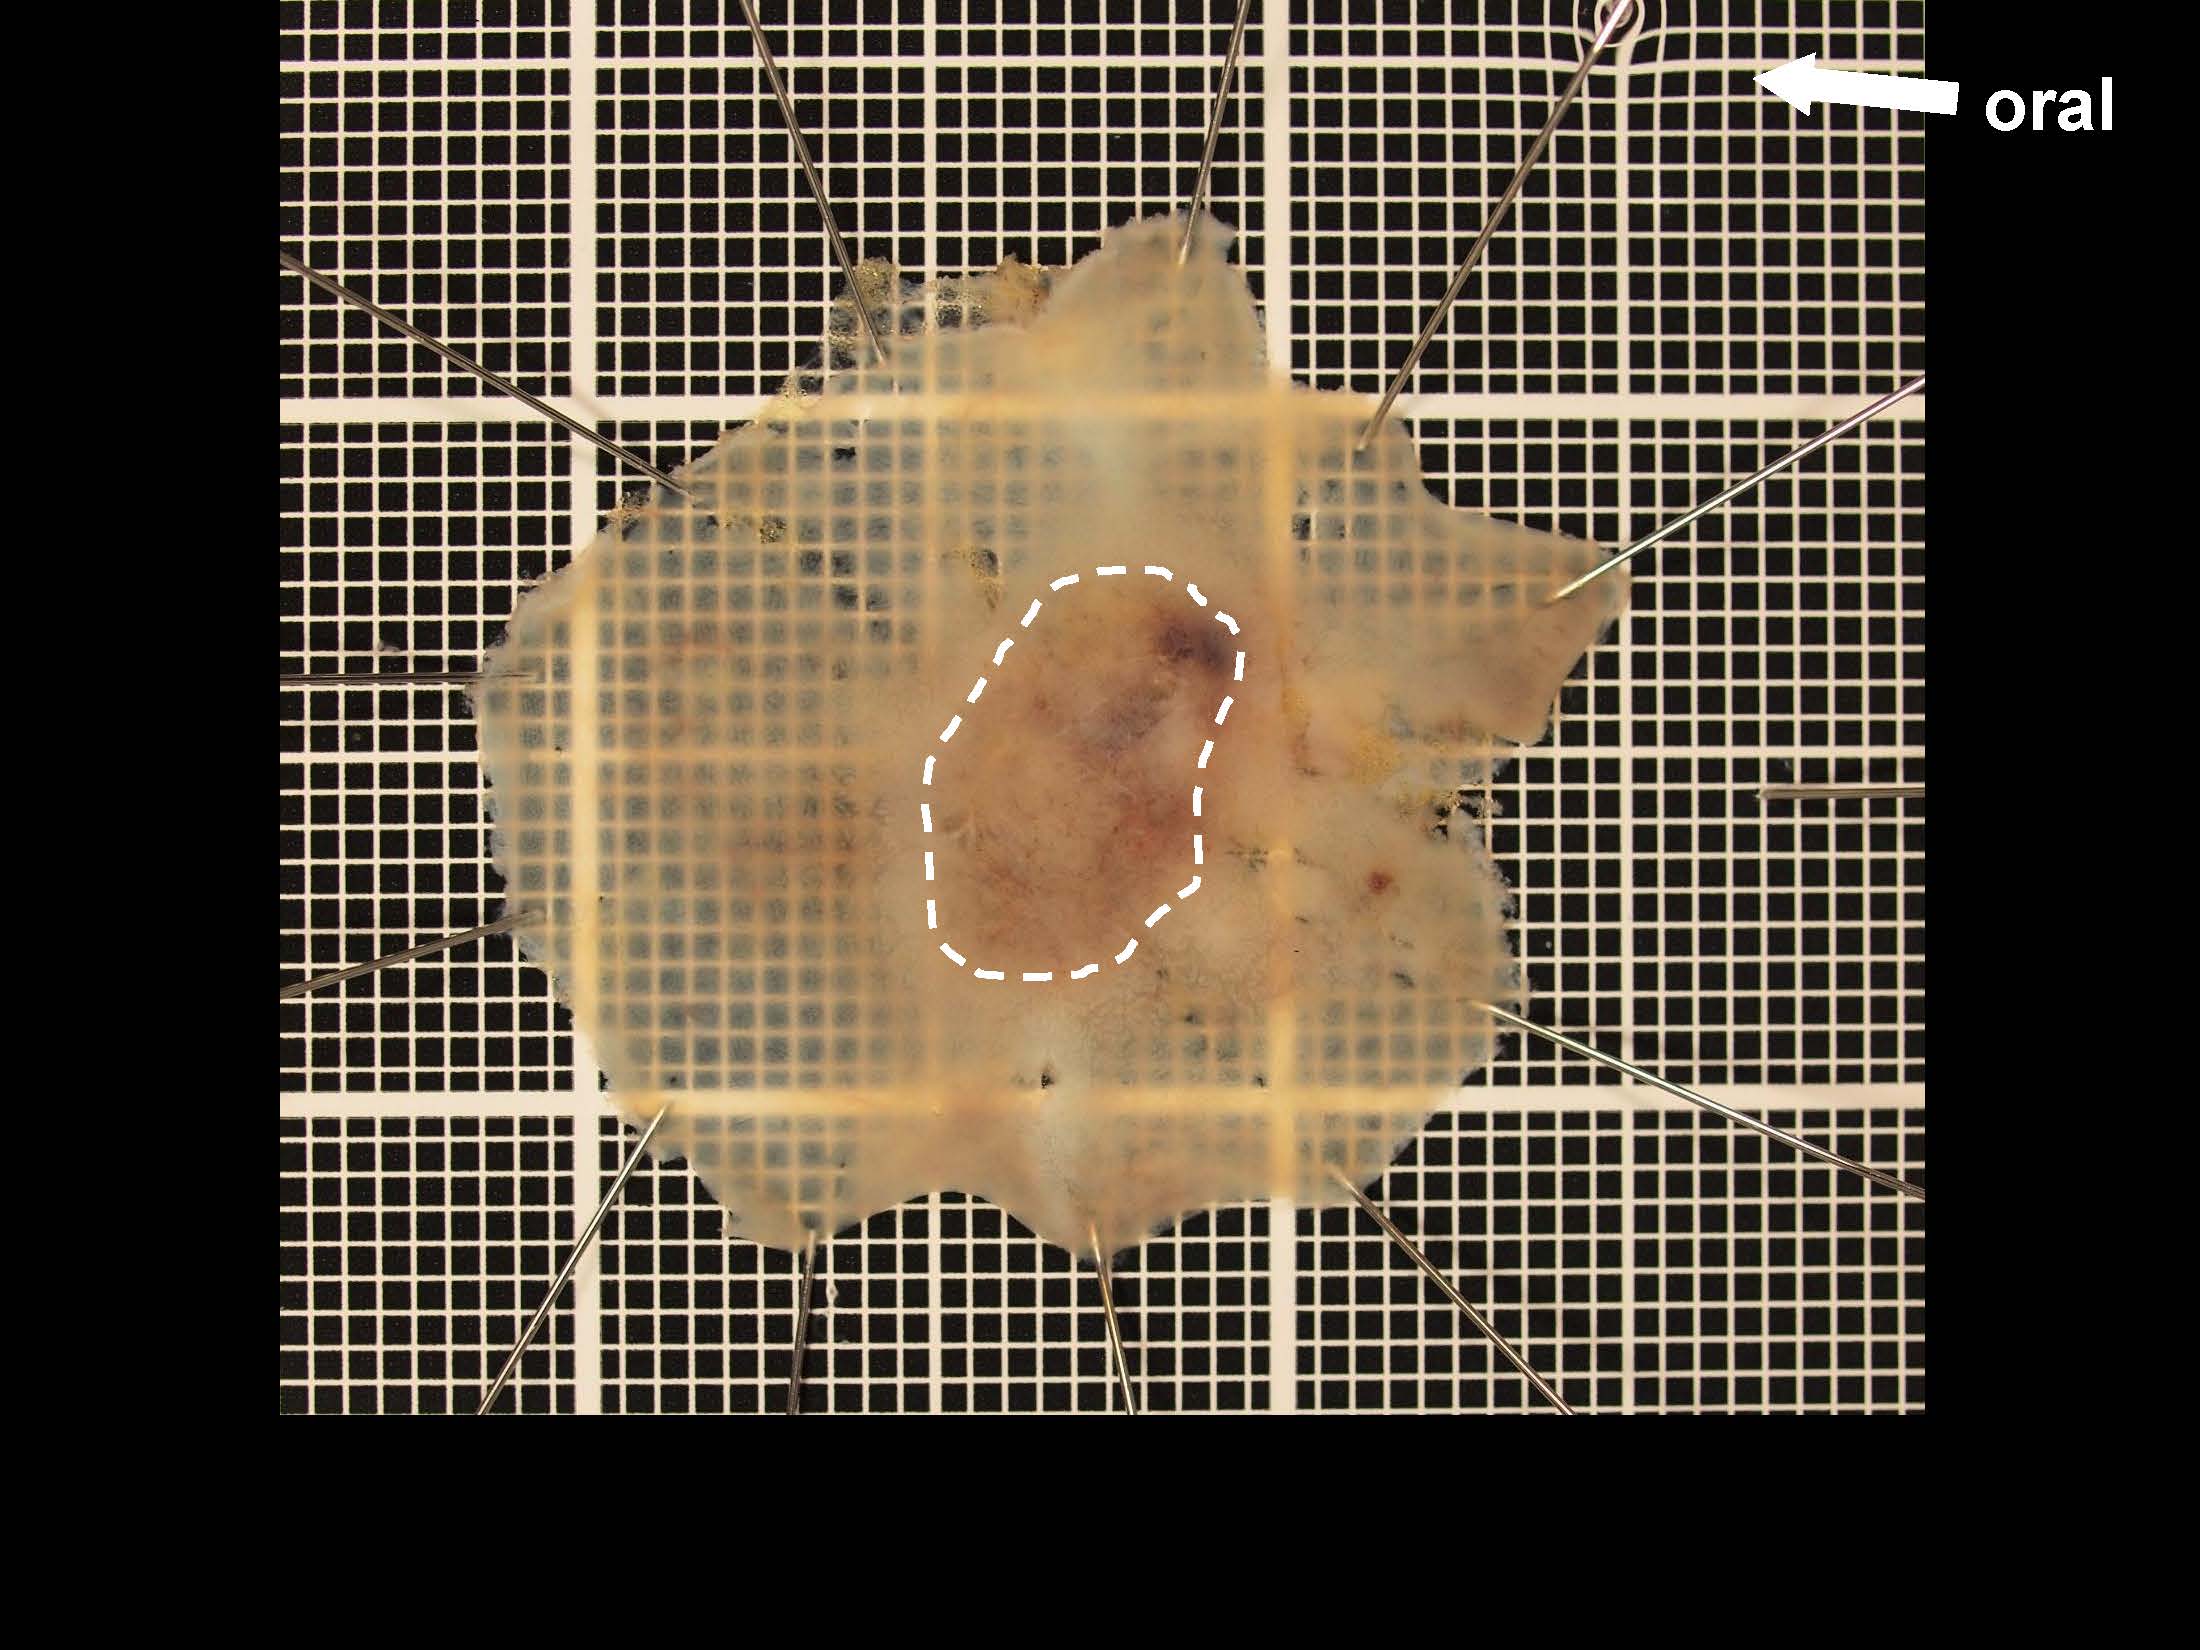

消化管Mapping~大腸~ 2021.10.27

消化管Mapping

消化管Mapping~大腸~

消化器内科

内視鏡検査・治療